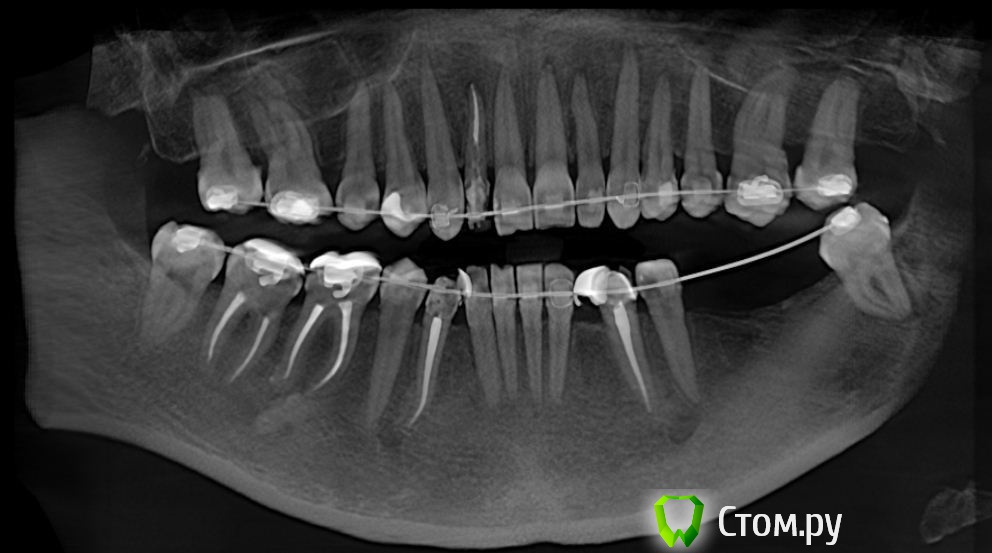

Эндж Опубликовано 30 июля, 2014 Поделиться Опубликовано 30 июля, 2014 Здравствуйте! Прокомментируйте, пожалуйста состояние моих зубов. Сейчас после ортодонтии и имплантации ношу пока времянки, через неделю планируется установка постоянных. Я вижу на двойке сверху гранулемуи мне кажется, что она увеличилась. Мой ортопед говорит, что канал хорошо пролечен и лучше не трогать, а я переживаю, что после установки постоянной коронки может начаться какая-нибудь проблема.Канал перелечили два с половиной года назад. Снимки:1) до перелечивания2) год назад3) и 4) вчера Ссылка на комментарий

red_butler Опубликовано 9 августа, 2014 Поделиться Опубликовано 9 августа, 2014 Скажите, пожалуйста, а вы видите в канале этого зуба СВШ? Доктор видит, а мне вроде его не ставили. И вопросик по остальным зубам с пролеченными каналами. Ортопед сказал, что во все каналы нужно поставить стекловолокно. Своих тканей на зубах вроде достаточно, премоляры депульпировали полностью здоровые, без пломб, только двойка сильна обточена.вкладки нет, похоже стоит стекловолокно. Эндодонтическое лечение зубов хорошее. Если судить только по снимку, я бы рекомендовал делать вкладки и коронки. Но единого мнения по этому вопросу нет. Нужен очный осмотр. 2 Ссылка на комментарий

Эндж Опубликовано 11 августа, 2014 Автор Поделиться Опубликовано 11 августа, 2014 Сегодня была у терапевта и ортопеда. Терапевт замерила гранулему на КТ сейчас и год назад. Сказала, что изменений нет. Посоветовала сейчас ничего не делать, ставить коронку. Если в будущем будут проблемы, сказала, то можно не снимая коронки сделать резекцию. Это правда? Или коронку придется менять?Ортопед не хочет, чтобы я подрезала десну для формирования уступа, говорит, что ниткой как-то отодвинет и все будет ОК. Такой вариант возможен? Или искать другого доктора. Ответьте, пожалуйста, мне в пятницу на прием, нужно определиться к этому времени. Ссылка на комментарий